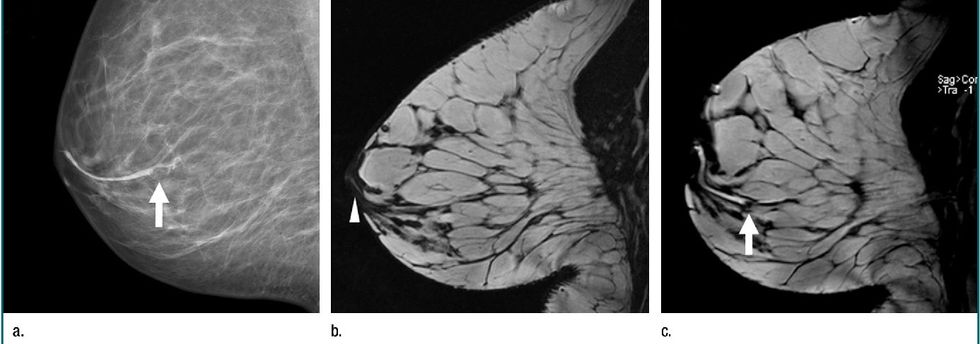

Mamografia është metodë diagnostike radiologjike, me të cilën mund të zbulohet kanceri i gjirit, mesatarisht 2 vite, para se gruaja me vetëkontroll ta palpon tumorin, andaj te gratë më të vjetra se 40 vjet, me aplikimin e mamografisë, mund të prevenohet 15-30% e vdekshmërisë nga kanceri i gjirit. Mamografia bëhet në dy drejtime: kraniokaudale dhe medio-laterale oblikve. Gjatë fotografimit, gjiri komprimohet me kompresor plastik, me ç’rast zvogëlohet trashësia e gjirit. Mbi gjinj është gypi i rëntgenit prej nga nëpër gjinj, kalojnë rrezet x të përshtatura trashësisë e dendësisë së tyre dhe regjistrojnë vizatimin e indit në filmin e rëntgenit të vendosur nën gjinj.

Ekzistojnë dy lloje të mamografisë: mamografia skrininge dhe mamografia diagnostike. Mamografia skrininge është ekzaminim i gjirit me rreze X te gratë që nuk kanë simptoma. Ka për qëllim zbulimin e kancerit të gjirit kur është me madhësi aq të vogël, sa që nuk mund të zbulohet me vetëkontroll ose me ekzaminim klinik.

Mamografia diagnostike përdoret për zbulimin e kancerit të mundshëm në gjinj te gratë që kanë shenja ose simptoma të sëmundjes. Shenjat ose simptomat mund të jenë: nodusi palpabil në gjinj, sekrecion nga gjiri, retrakcion i mamillës, retrakcion i lëkurës ose ndonjë ndryshim tjetër në gjinj.

Rezonanca Magnetike (RM) rekomandohet si metodë skrininge tek gratë me predispozitë gjenetike – ndërrime në gjenin BRCA 1 dhe BRCA 2. RM është shumë e saktë në vlerësimin e përgjigjes së tumorit në kimioterapinë neoadjuvante dhe kimioterapinë primare si dhe në diferencimin në të mes tumorit të mbetur dhe fibrozës. RM ka rëndësi në diagnostikimin e karcinomës multicentrike në gjinj, diagnostikimin e përfshirjes së limfonodeve aksillare, diagnostikimin e dëmtimit të mundshëm nga radioterapia të fijeve nervore axillare etj.

RM luan rol të rëndësishëm në zbulimin e rupturave të implanteve të silikonit në gjinj te gratë që i janë nënshtruar intervenimeve kirurgjike kozmetike. Te më pak se 2% e pacientëve me limfonode palpabile në aksillë, mamografia dhe ultrazëri janë negative. Disa studime kanë treguar se RM mund të zbulojë kancerin, i cili nuk shihet në mamograf deri në 33% të pacientëve.